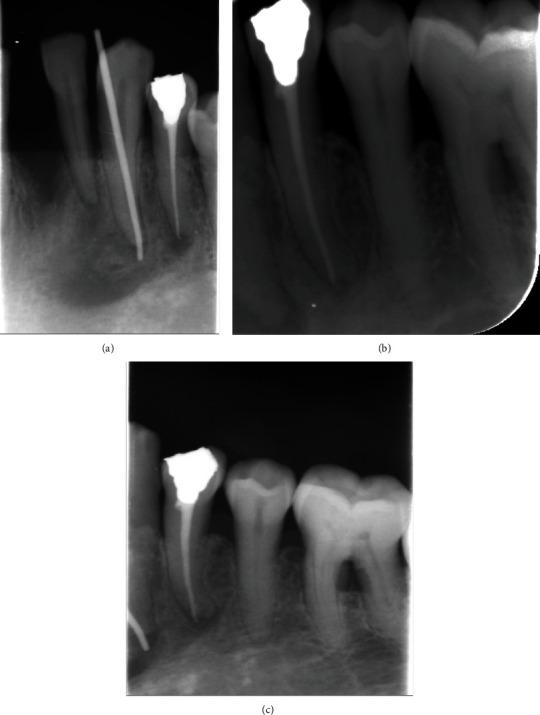

Actinomycosis is gram-positive saprophytic infection that is characterized by chronic suppurative and granulomatous lesion. It could be found in the oral cavity, lungs, colon, and genital area. In the oral cavity, it is commonly associated with infected root canals presented as persistent infections. This case reports demonstrate an atypical presentation of actinomycosis in the lower left mandibular canine/premolar area showing painless soft tissue lesion associated with bone sequestration. Nonsurgical curettage of the lesion followed by nonsurgical root canal treatment and retreatment to the offended teeth was determined as the treatment modality for this case.

放线菌病是一种革兰氏阳性腐生菌感染,其特征为慢性化脓性和肉芽肿性病变。它可发生于口腔、肺部、结肠和生殖器区域。在口腔中,它通常与表现为持续性感染的感染根管有关。本病例报告展示了左下下颌尖牙/前磨牙区放线菌病的非典型表现,表现为与骨坏死相关的无痛性软组织病变。确定对该病变进行非手术刮治,随后对患牙进行非手术根管治疗和再治疗作为该病例的治疗方式。